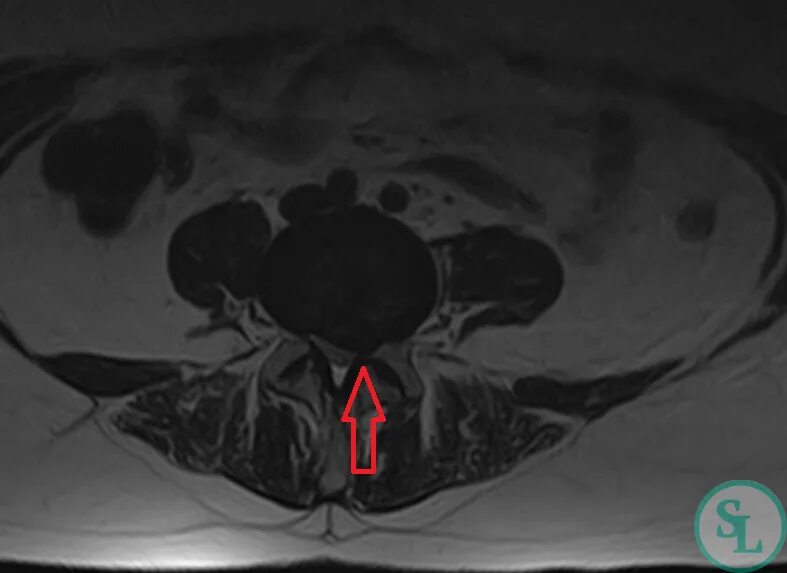

Грыжа диска l5 лечение